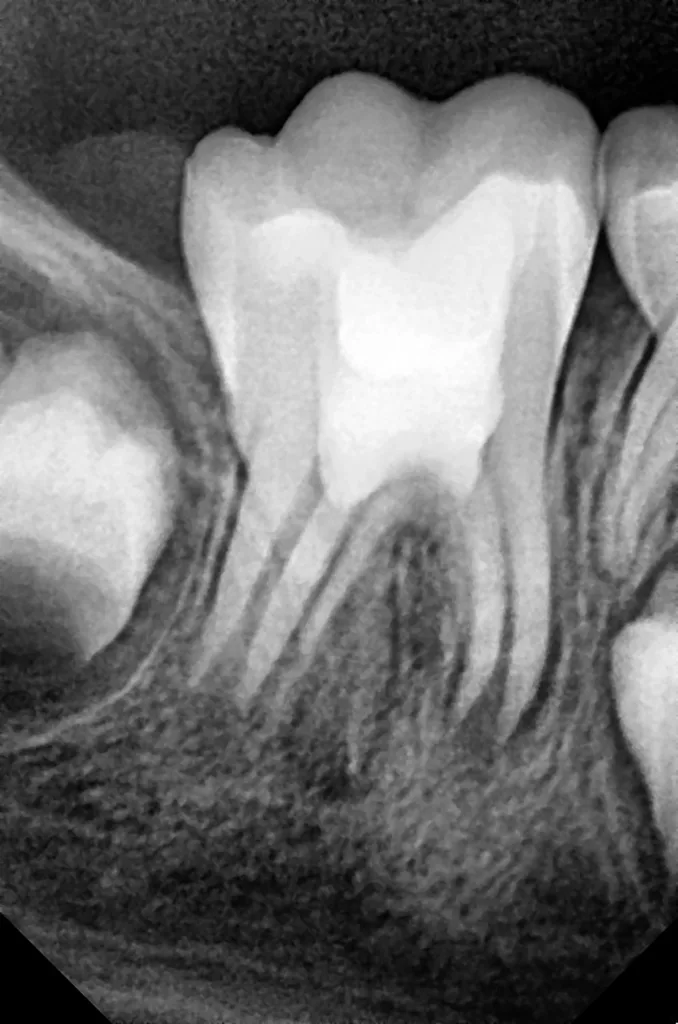

Bei routinemäßigen Röntgenkontrollen ergeben sich manchmal Zufallsbefunde unklarer Genese. So stellt sich beispielsweise bei der Betrachtung der Abbildung 1 die Frage, wie sich ein Zahnhartsubstanzdefekt so schnell entwickeln konnte. Ein weiteres Röntgenbild (Abb. 2), das vor dem Zahndurchbruch aufgenommen wurde, zeigt jedoch, dass es sich in diesem Fall nicht um Karies, sondern um die sogenannte präeruptive intrakoronale Resorption (PEIR) handelt. Für diesen Befund finden sich in der Fachliteratur auch noch andere Bezeichnungen wie „idiopathic external resorption of unerupted permanent teeth“ [1], „intra-follicular caries“ [2], „radiolucent lesions resembling caries“ [3], „occult caries“ [ 4] oder „pre-eruptive caries“ [5].

Das fünfjährige Mädchen stellte sich 2017 zur jährlichen Routinekontrolle vor. Im Rahmen der Untersuchung wurden Röntgenaufnahmen der Milchmolaren gemacht (Abb. 2). Der klinische und radiologische Befund der vor uns früher gelegten Kompositfüllungen war gut, es wurde allerdings eine PEIR an den noch nicht durchgebrochenen ersten bleibenden Molaren festgestellt (Abb. 2). Den Eltern wurde empfohlen, sich unverzüglich bei Beginn des Durchbruchs der ersten Molaren erneut zur Behandlung vorzustellen. Ein Jahr später erschien die junge Patientin schmerzfrei zur Kontrolle. Der Zahn 36 war noch teilweise mit Gingiva bedeckt. Auf einer neuen Röntgenaufnahme (Abb. 1) wurde die PEIR-Läsion mit unveränderter Größe in pulpanahen Bereichen bestätigt (Grad 3 der Läsion nach Seow). Der Zahnschmelz sah intakt aus, es konnte kein pathologischer periapikaler Befund bei den noch nicht ausgewachsenen Zahnwurzeln festgestellt werden. Daraufhin wurden die verschiedenen Behandlungsmöglichkeiten von Fissurenversiegelung bis Vitalerhaltung der Zahnpulpa mit den Eltern des Kindes besprochen.